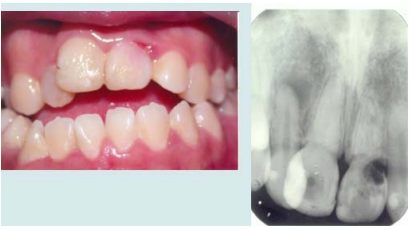

14.如下圖,患者左上正中門齒出現顏色異常,自述有外傷病史,臨床檢查發現,牙齒於唇-遠心側 齒頸部有一窩洞,放射線檢查亦顯示大量的齒質破壞,下列診斷何者最貼切?

(A)牙齒表面吸收(surface resorption) (B)齒頸部外吸收(cervical external resorption) (C)牙齒內吸收(internal resorption) (D)取代性吸收(replacement resorption)